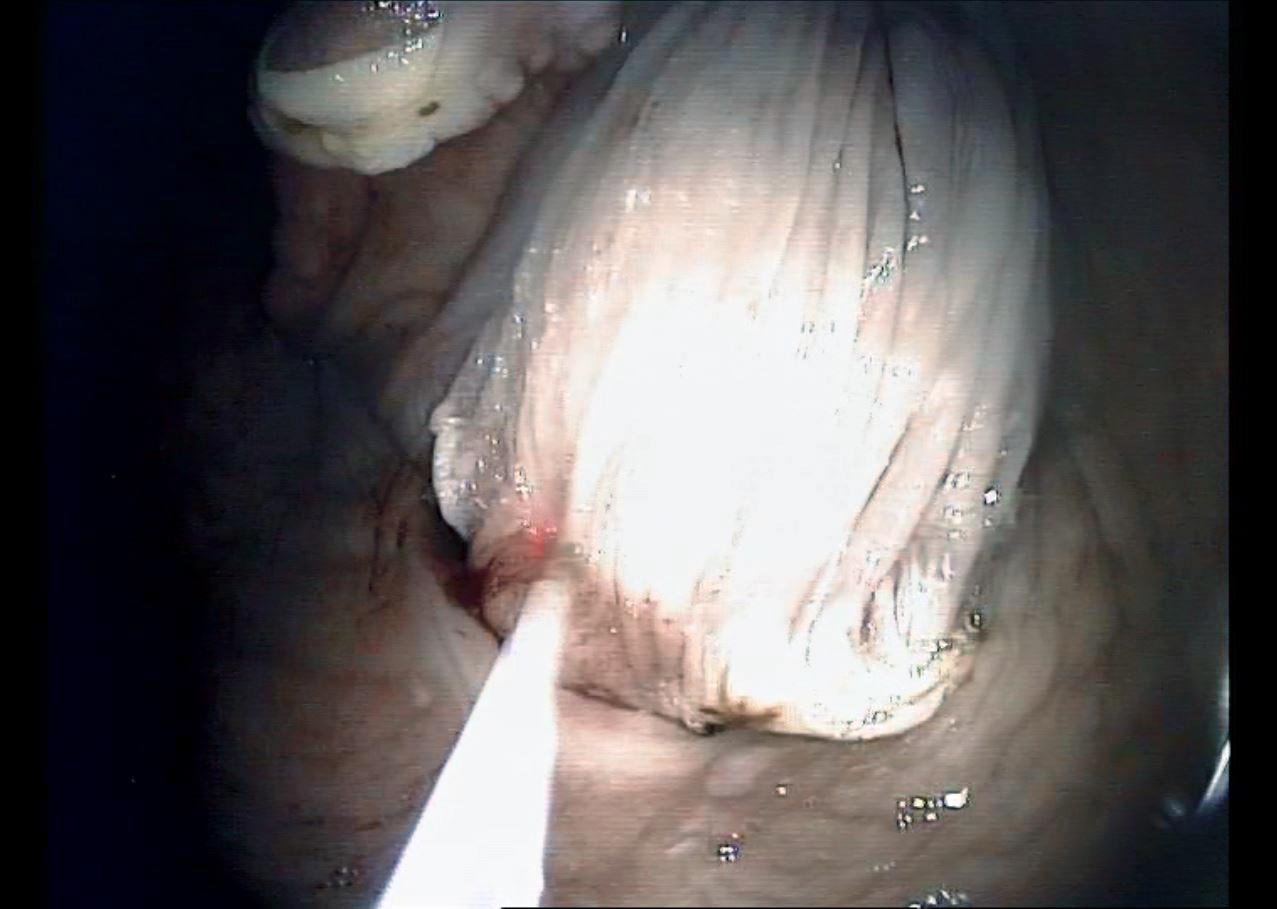

A transendoscopic lance was used to penetrate the cyst and aspirate approximately 15ml of serous fluid (Figure 2). This partially deflated the cyst, easing manipulation and assisting in dissection. With endoscope in situ, curved bronchoesophageal grasping forceps were passed through the contralateral nasal passage and used to manipulate the cyst (Figure 3). A transendoscopic diode laser was used to excise the cyst en bloc, along with the overlying subepiglottic mucosa using a contact technique (Figures 4 and 5). Following excision, topical dexamethasone sodium phosphate (total 20mg) was applied to the surgical site.